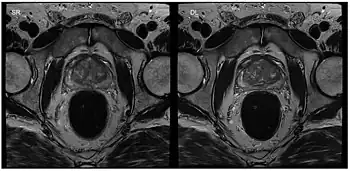

MRI-guided invasive procedures

Applications in interventional MRI, which refers to the monitoring of minimally invasive surgical procedures, are possible by interactively changing parameters such as image position and orientation. This application is particularly helpful when a 3D image of the tissue is needed during surgery.[10] It requires an in-room display for the physician to use during the procedure as well as the use of MRI-safe surgical tools. These include ceramic, plastic, or titanium, which is a paramagnetic metal. By using bSSFP and parallel imaging with multiple coils, frame rates of 5-10 frames per second have been accomplished, allowing for the visualization of cardiac procedures.[10]